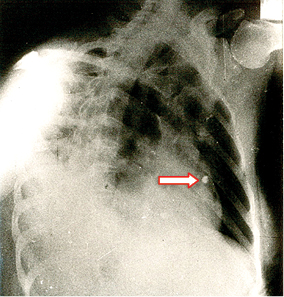

Llegó al hospital, en ambulancia y atendido por paramédicos, un individuo de sexo masculino, de 24 años de edad, con una herida de bala en el hemitórax izquierdo, sin orificio de salida. El paciente se encontraba razonablemente estabilizado, con dos venas canalizadas y oxígeno. Estaba consciente y declaró que su vecino le disparó como a tres metros de distancia por una discusión. Las vías respiratorias estaban permeables, la TA 82/44, con 124 latidos cardiacos por minuto. Las radiografías de tórax localizaron el proyectil en el espesor de la pared del ventrículo izquierdo (Figura 1). El orificio de entrada era nítido y se ubicaba ligeramente arriba de la tetilla izquierda, a cinco centímetros del borde izquierdo del esternón. El sangrado externo no era profuso. Bajo anestesia general, se realizó toracotomía anterolateral a la altura del quinto espacio intercostal. Se aspiraron 80 mL de sangre de la cavidad pleural. En el lóbulo superior izquierdo del pulmón se identificó la herida, que prácticamente no sangraba y dejaba escapar muy poco aire. El pericardio se encontraba perforado por el proyectil. Existía hemopericardio, pero sin llegar a tamponade, seguramente debido a que el proyectil incrustado en el espesor del ventrículo lo impedía. Se procedió enseguida a abrir el pericardio en toda su longitud, separando los bordes con suturas a tracción con objeto de tener un campo visual operatorio adecuado. La herida de la bala se localizó en la parte alta del ventrículo izquierdo, muy cerca de la arteria coronaria descendente anterior. No era nítida e iba a ser difícil repararla. El proyectil no se visualizó. Tratamos de localizarlo en el espesor del músculo, pero sin lograrlo. Con cada latido del corazón, escapaba escasa cantidad de sangre por la herida. No intentamos emplear una pinza de Allis por temor de ampliar la herida o lesionar la coronaria. En vista de la situación, decidimos explorar el interior del ventrículo a través de la orejuela. La aurícula, válvula mitral y estructuras subvalvulares se encontraron completamente normales, pero la bala no se halló. Solicitamos la presencia de los técnicos en imagenología en el quirófano para tratar de ubicar el proyectil por medio de radiografías. En el tórax, los resultados fueron negativos, pero en la placa de abdomen se visualizó el proyectil a escasa distancia del riñón derecho. Se procedió de inmediato a suturar cuidadosamente la herida cardiaca con Prolene 2-00 con tres puntos en “colchonero” verticales anclados con teflón, tratando de no involucrar a arterias coronarias y cerciorándonos de que no sangraba. La toracotomía se cerró, dejando dos sondas de drenaje sin succión. Acto seguido, se reposicionó al sujeto para realizar la intervención adecuada, con objeto de recuperar la bala. El proyectil, calibre 22, se encontraba en el interior de la arteria renal derecha antes de su división (Figura 2). Se procedió a retirarlo, reparando enseguida el vaso. El herido evolucionó satisfactoriamente. Fue externado a los siete días. Se revisó a las dos semanas y se le observó muy bien.